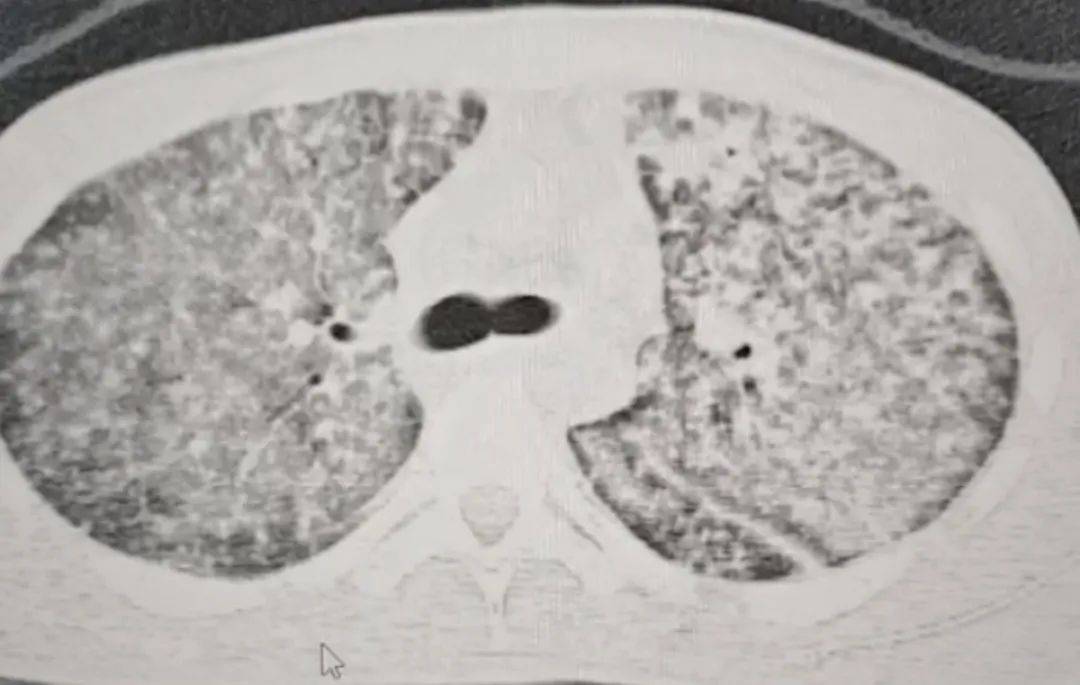

检查结果令医生大为震惊如何代理皇冠信用盘 。肺部 CT 影像显示,小王的肺部几乎全白。

同时,指脉氧检测结果也极不理想,正常人的氧合指数在400-500左右,而小王的氧合指数仅有100如何代理皇冠信用盘 。

这意味着,小王喘气次数远超常人,可体内氧气含量却远不及常人如何代理皇冠信用盘 。医生怀疑小王患上了肺结核,且病情已十分严重,当即建议他转诊至郑州的大医院。

“他来我们医院时,我一看CT,双肺都呈现弥漫性病变,考虑白肺,情况十分危急如何代理皇冠信用盘 。” 河南省胸科医院结核内科六/ 感染危重症病区主任梁瑞霞向大河报·豫视频记者讲述,小王因肺部感染引发了急性呼吸窘迫综合征。

三天后,小王的生命体征逐渐趋于稳定如何代理皇冠信用盘 。十天后复查肺部CT,病区有明显改变。